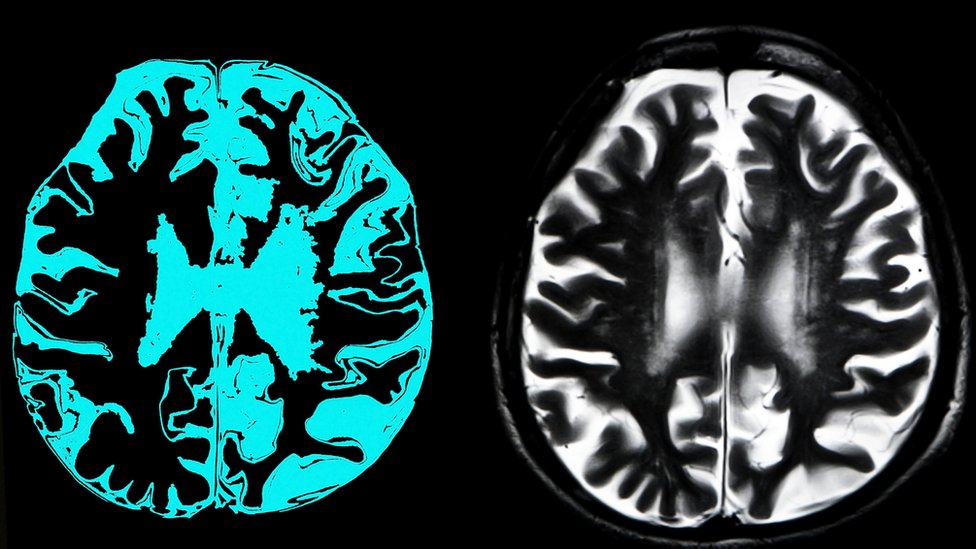

- Pet načina da prepoznate simptome Alchajmera

- Izlečiva bolest koja se često pobrka sa Alchajmerom

- Bivši fudbaleri imaju tri i po puta veću šansu da umru zbog demencije